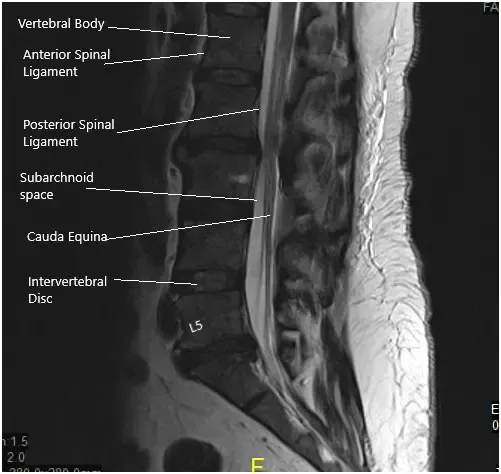

MRI of the lumbosacral spine in sagittal and axial views.

A 50-year-old male patient who started experiencing excruciating pain down his left leg with weakness in that leg and numbness in his peroneal region. His sensory deficit included his lateral thigh and entire foot as well. He obtained an MRI that showed a disk fragment compressing on the L5 and S1 nerve roots with severe lumbar stenosis in the lateral recess and encroachment on the left side at L5 and S1.

Grade I anterolisthesis of L2 on L3. Straightening of the lumbar lordosis. Degenerative changes are identified diffusely within the lumbar spine. At L5-S1, there is a left-sided disc herniation/protrusion causing mild narrowing of the thecal sac and narrowing of the left lateral recess. This encroaches upon the left S1 nerve root within the left lateral recess.

The hernia also extends into the proximal left neural foramen causing mild narrowing. The mild right neural foraminal narrowing is also visualized. Mild to moderate narrowing of the thecal sac is identified at L2-3.